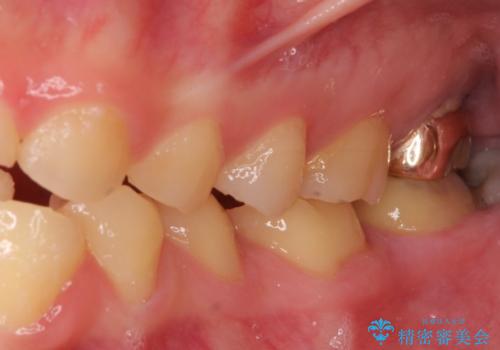

- 一時期の拒食症に伴い歯が酸で溶けてボロボロになってしまったとのことで来院された患者様です。

酸によりエナメル質の大半が溶けており、下顎前歯以外は酷いむし歯のような状態でした。